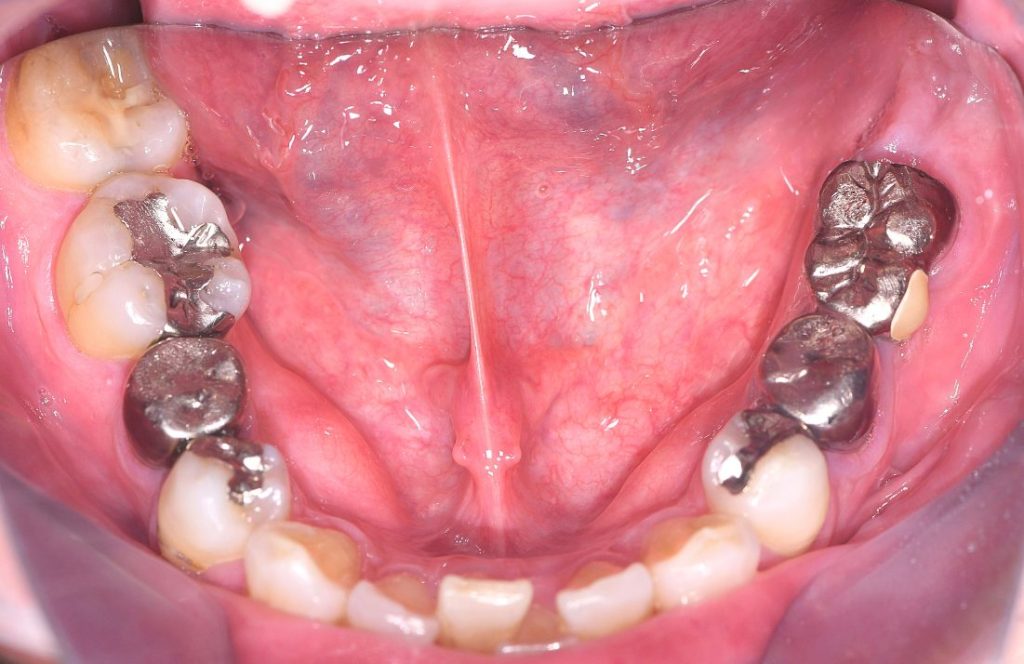

来院時の口腔内写真

抜歯から3ヶ月経過後

左下6、左下7:インプラント

左下5:カンチレバー

年齢    50代・男性

主訴①左下5歯根破折による痛み

治療内容インプラント治療(ストローマン)

費用¥1,100,000(税込)

期間約10ヶ月